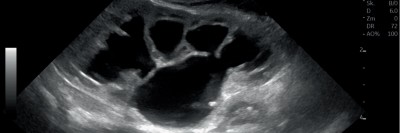

Ein Knubbel in der Wange – an welche Diagnose denken Sie?

Nach wiederholten Besuchen bei Kinder-, HNO- und Zahnärzten steht nun die 11-jährige Patientin vor Ihnen. Sie leidet seit zwei Jahren unter belastungsabhängigen Schmerzen beim Kauen. Nachdem eine vorausgegangene Sonographie und ein vergrößerter Lymphknoten eine Raumforderung im M. masseter vermuten lassen, sehen Sie nun diese MRT-Bildgebung.